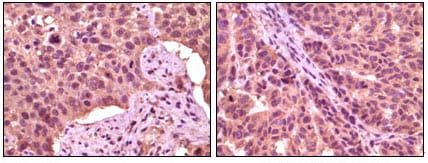

IHC 1/200 - 1/1000 Human,Mouse,Rat

**摘要**: 利用特异性GSK3α抗体,作者发现心脏缺血再灌注损伤中,GSK3α通过磷酸化DRP1蛋白调控线粒体分裂。抗体在实验中被用于免疫沉淀和免疫组化,证实GSK3α的亚细胞定位及功能。